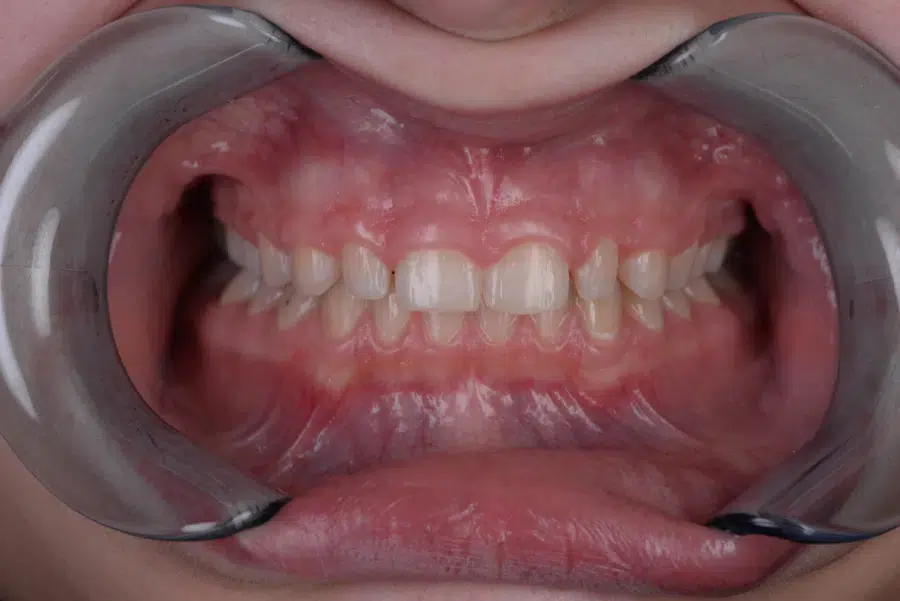

După

Caz de estetică dentară – Fațete ceramică presată E-Max

Provocarea acestui caz a fost în prepararea minim invazivă a dinților centrali rotați și a obține o formă și o culoare cât mai naturală, pacienta dorind un caz de estetică dentară ce să nu fie observabil.

Pacienta a beneficiat de corecție gingivala cu laser pentru uniformizarea asimetriilor gingivale, tratamente endodontice de canal sub microscop, obturațiile vechi (plombe) schimbate cu materiale de compozit cu particule nanoceramice, și fațete dentare din ceramică presată E-Max.

Termen de finalizare 2 săptămâni de la amprentarea finală.